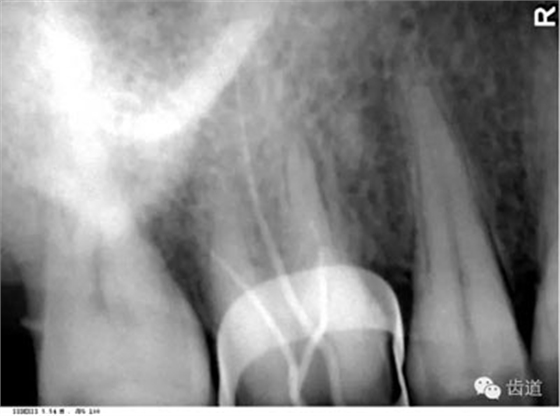

在投照上頜磨牙根尖片時(shí),經(jīng)常可以看到牙根上方有一密度低的影像,為上頜竇的一部分,邊緣環(huán)繞以密度高的線狀影像,為上頜竇壁致密骨層。有時(shí)可見(jiàn)上頜竇的分隔。

可在第一、二磨牙根尖上方或重疊在牙根上為近似三角形或半圓形密度高的影像。

常在上頜第二、三磨牙的牙冠區(qū)域有一較牙密度稍低由后伸向前方的三角形影像。

在最后一個(gè)磨牙遠(yuǎn)中區(qū)域,其邊緣向后上,X線片上常呈稀疏的網(wǎng)狀結(jié)構(gòu),為正常疏松區(qū)。

在上頜結(jié)節(jié)后方,呈長(zhǎng)條狀邊緣整齊、寬約0.2cm、長(zhǎng)約1cm、直的或下端略向后方彎曲的密度稍高的影像。